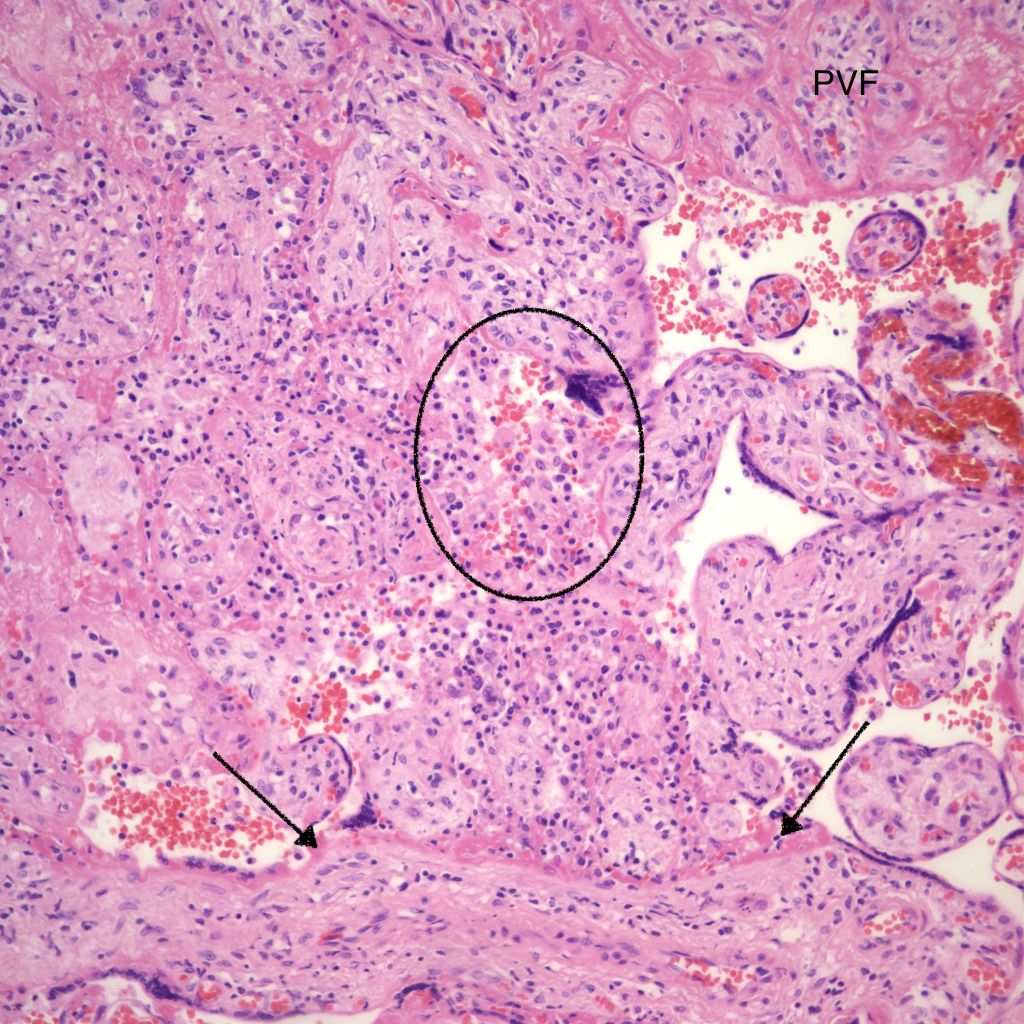

Low Grade CHIV (5-50% of the intervillous space occupied by monocytes)

There is a focus of intervillous fibrinoid with no definite cytotrophoblast that is not re-covered with syncytium suggestive of recent syncytial injury (F). (10x, H&E)

CHIV with prominent perivillous fibrinoid deposition